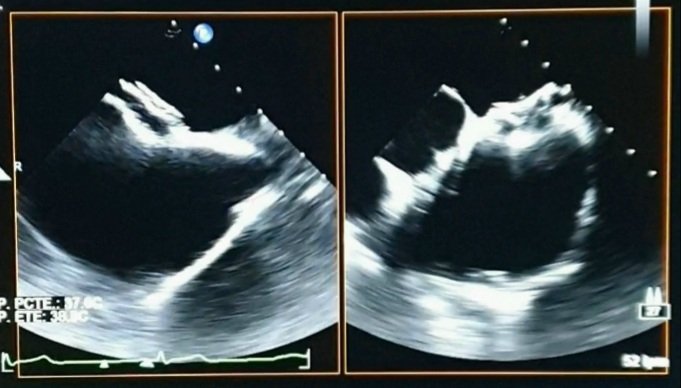

@PicabeaSofia 👌👌 Falta la adquisición tardía para confirmar trombo.

@MaxicRossi Tiene FA y defecto de relleno en OI en fase arterial

Pciente 40 años, sin antecedentes CV. Presenta 4 meses de evolución disnea CF II + palpitaciones. Ecocardio evidencia CIA.

Excelente ETE 3D como guía de cierre de CIA. Muy didáctico. @MaxicRossi @leolasave @drchavez_ruben @ComiteIcr @AnibalDamonte (ver hilo)